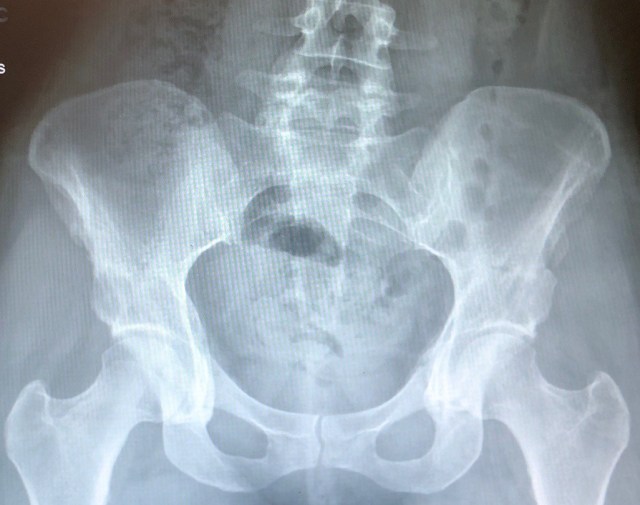

I’ve attached a letter that I received my surgeon that is very meaningful.